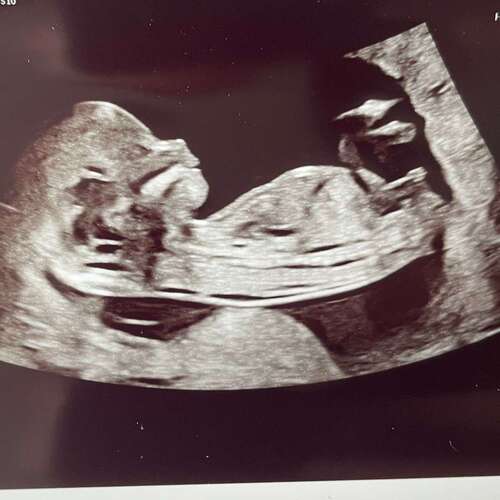

13+1 weken

Deze is gisteren gemaakt tijdens de 13 weken echo.

Ik ben super benieuwd 💗💙